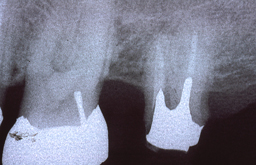

下の画像はレントゲン写真になります。レントゲンの見方ですが、向かって左がその患者さんの右になります。ちょうど向かい合わせになっていると思ってください。硬いところ(金属、歯、骨)は白く映り、柔らかいところ(歯肉、頬、唇)はほとんど黒くなって映りません。(根の中の白いのは硬いものではなくバリウムの様な造影剤が入っています

この患者さんは左上が4本なく、左右の下は3本ずつ合計で6本歯がありませんでした。そのため上下で入れ歯を入れていました。

娘さんが矯正治療で歯を4本抜くことになった為、その4本をお母さん(この患者さん)に植えることにしました。

■症例(術後)

右の画像は娘さんの歯を4本植えたところです。左上に2本、左右の下に1本ずつ植えています。その為入れ歯がなくても噛めるようになりました。しかし下は約5年しか使えませんでした。免疫反応で体が要らないものだと、吸収してしまうのです。上は10年以上使えています。